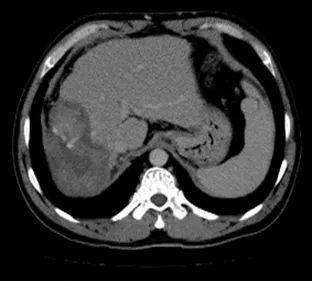

1. 肝脏原发病灶治疗前后磁共振扫描结果对比

淫羊藿素软胶囊治疗3、6、16、18个月后,肝脏病变呈现消融后改变,未观察到病灶进展。

治疗前

治疗3个月